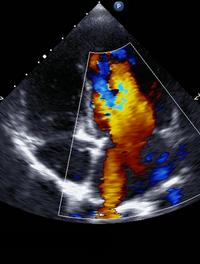

Le rétrécissement aortique (RA), valvulopathie la plus fréquente, est une pathologie évolutive associée à une morbidité et une mortalité [...]

En présence de la défaillance d’une prothèse mitrale on dispose de peu de données comparant le devenir des patients selon qu’ils sont [...]